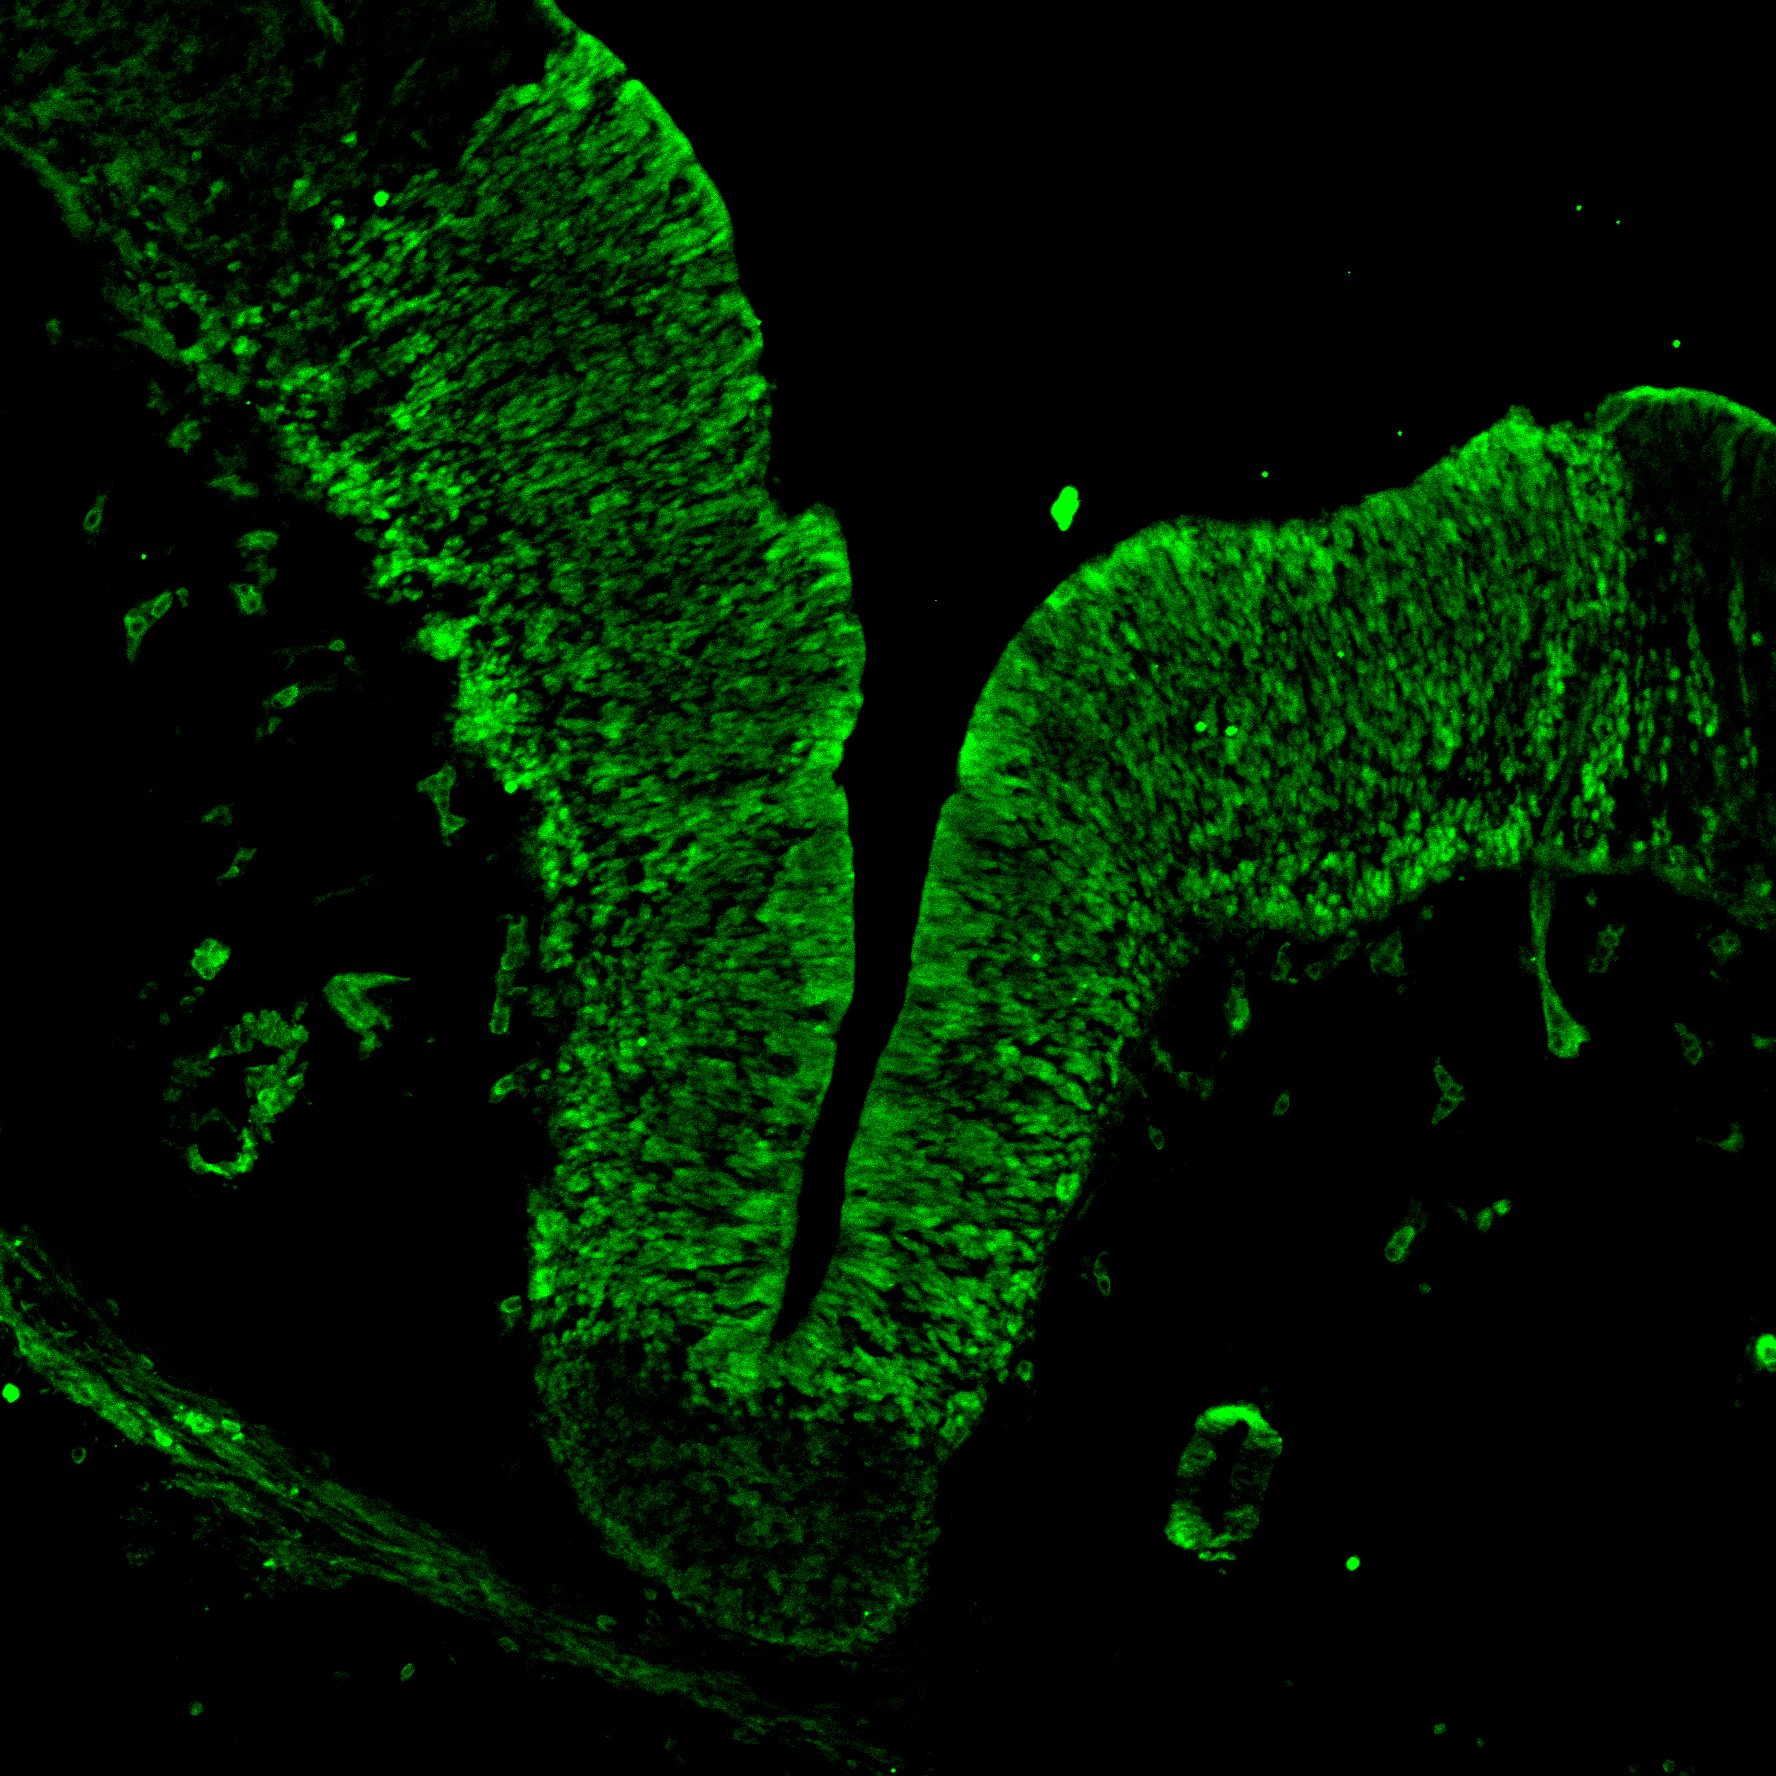

An anatomical analysis of the developing human midbrain from 6 post-conceptional weeks (PCW) to 22 PCW reveals increased tissue complexity, characterized by the emergence of dopaminergic nuclei, as highlighted by immunofluorescence analysis for tyrosine hydroxylase (TH).

OTX2

6PCW human midbrain